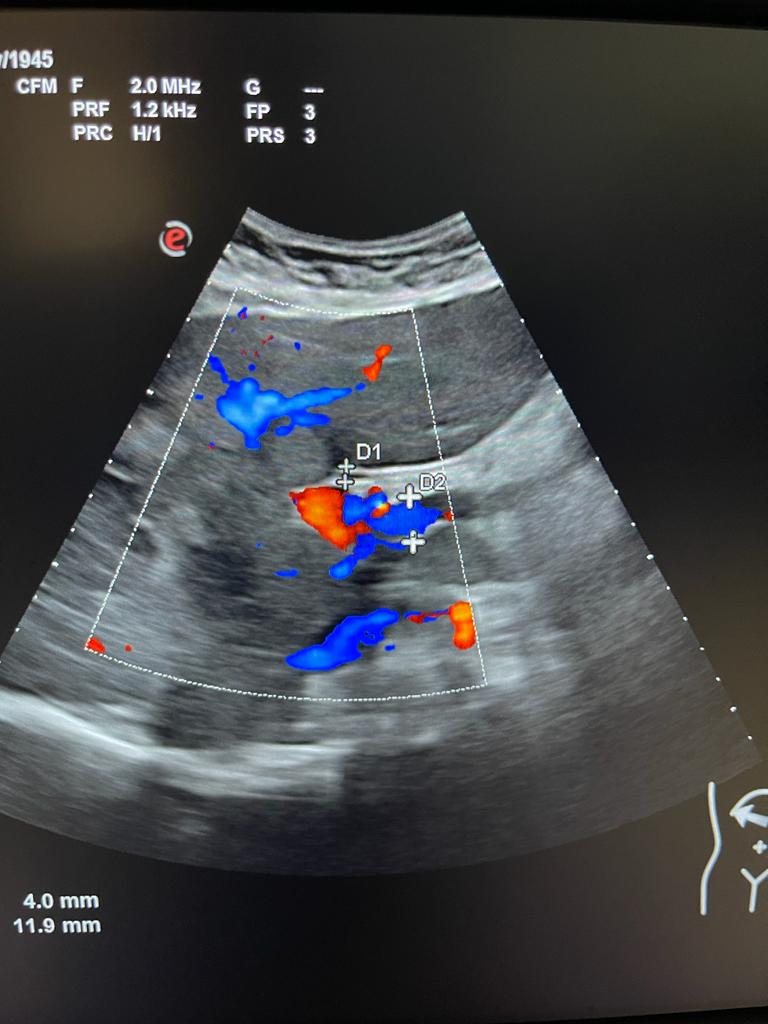

Se aprecia hígado heterogéneo con múltiples LOES hepáticas hiperecogénicas (una de ellas de unos 7x7 cm), sin captación de doppler. Al menos otras 2 LOES de menor tamaño presentan halo hipoecoico. Vesícula replecionada de contornos lisos y sin litiasis en su interior. Ambos riñones visualizados de tamaño normal y sin datos de hidronefrosis.

Se decide pedir ecografía reglada para valorar estudio posterior. Ecografía confirma sospecha de LOES intrahepáticas. Desde radiología amplian estudio con TAC: lesión ósea lítica con criterios de agresividad expansiva con masa de partes blandas en vertiente posterior de pala ilíaca izquierda.